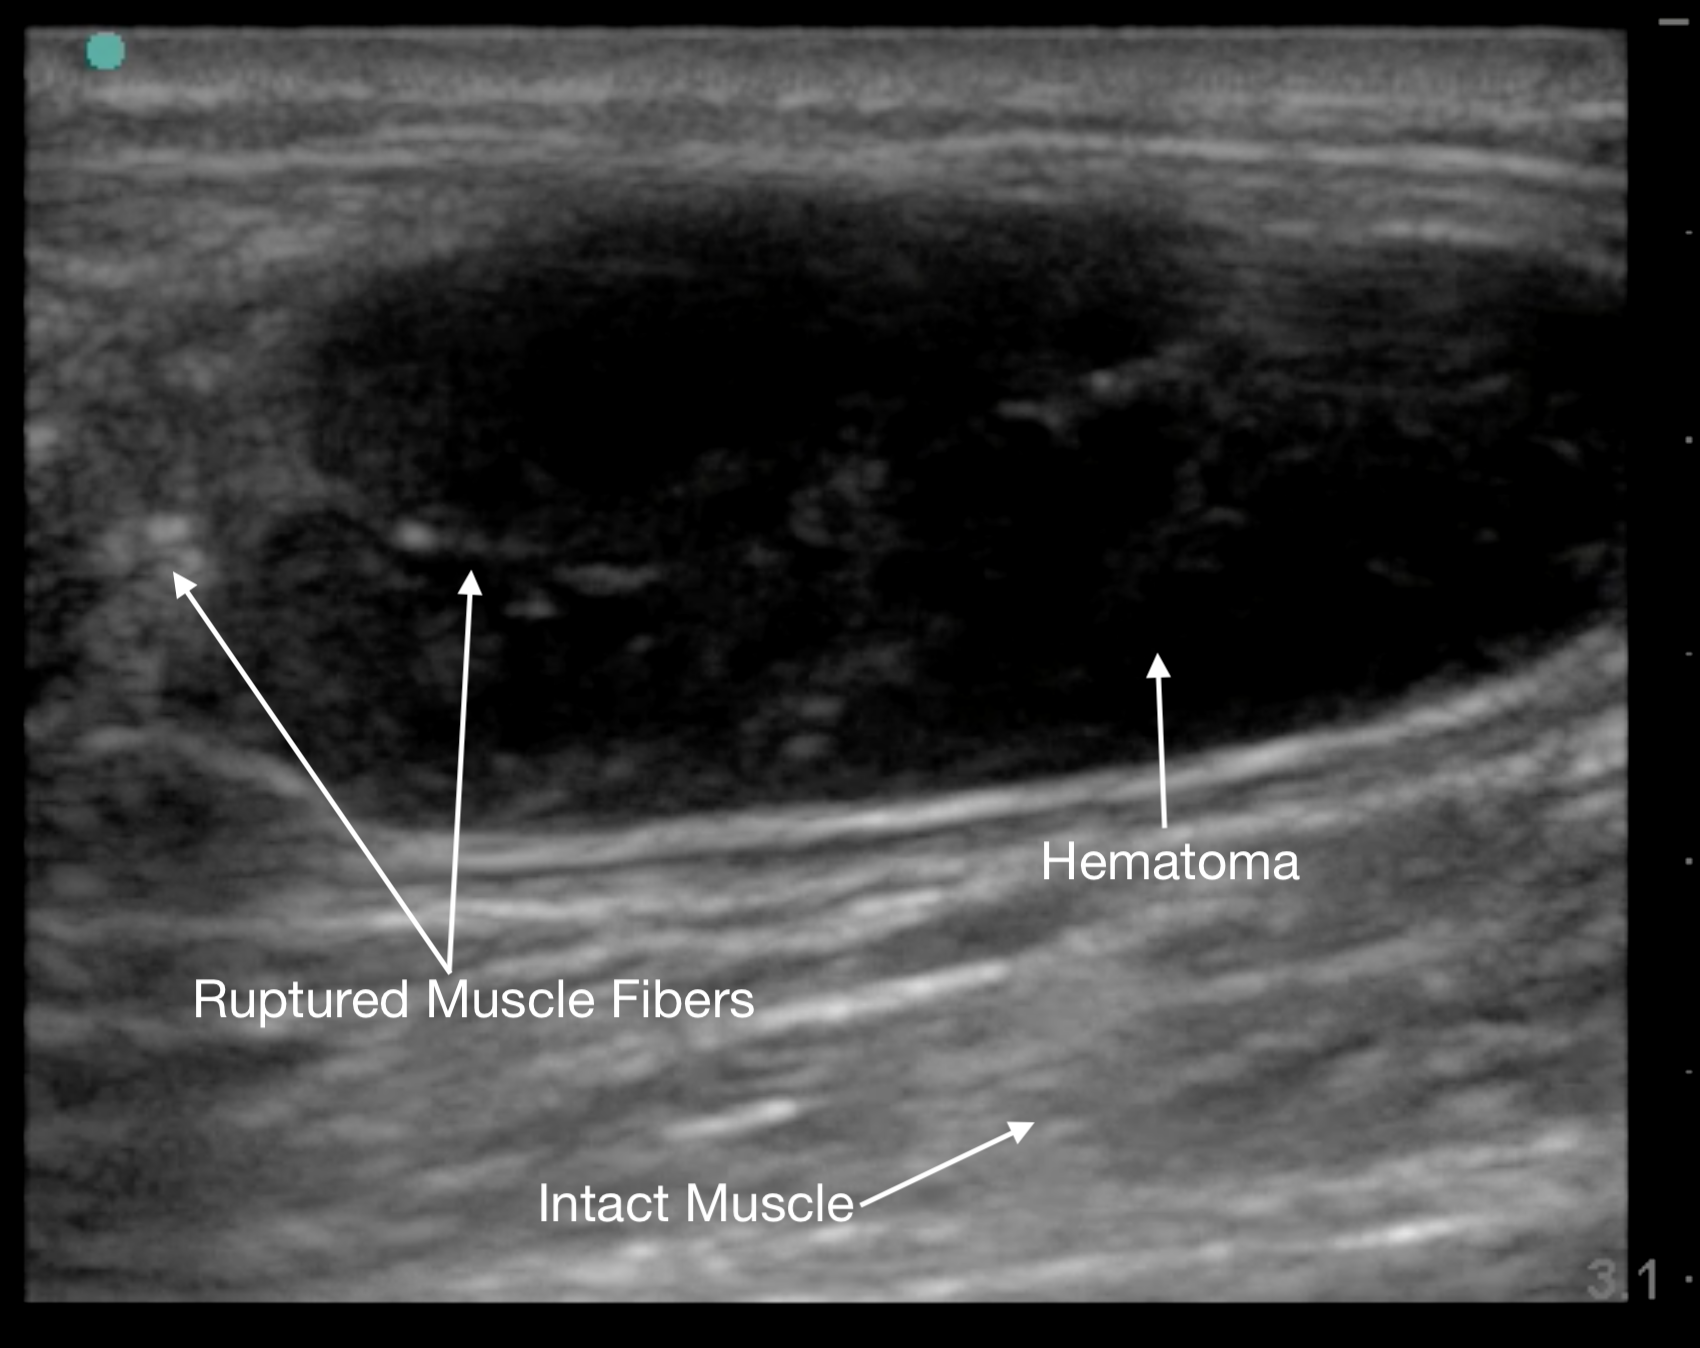

Muscle, Tendon and Ligament Injuries

Muscle tears in biceps femoris, rectus femoris, and gastrocnemius will show a discontinuity in the muscle belly and adjacent hematoma. The associated “clapper in bell” sign is the retracted upper portion of torn muscle fibers (clapper) surrounded by hematoma (bell).19

Figure 12.

Gastrocnemius muscle tear in short axis at its proximal end.